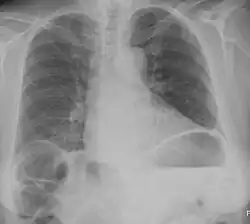

Chest X-ray showing obvious Chilaiditi's sign, or presence of gas in the right colic angle between the liver and right hemidiaphragm.

Chilaiditi syndrome is a rare condition when pain occurs due to transposition of a loop of large intestine (usually transverse colon) in between the diaphragm and the liver, visible on plain abdominal X-ray or chest X-ray.[1]

Normally this causes no symptoms, and this is called Chilaiditi's sign. The sign can be permanently present, or sporadically. This anatomical variant is sometimes mistaken for the more serious condition of having air under the diaphragm (pneumoperitoneum) which is usually an indication of bowel perforation, possibly leading to surgical interventions.